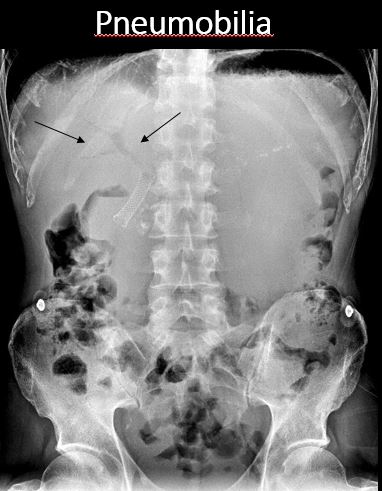

There is pneumobilia. |

No | NA |